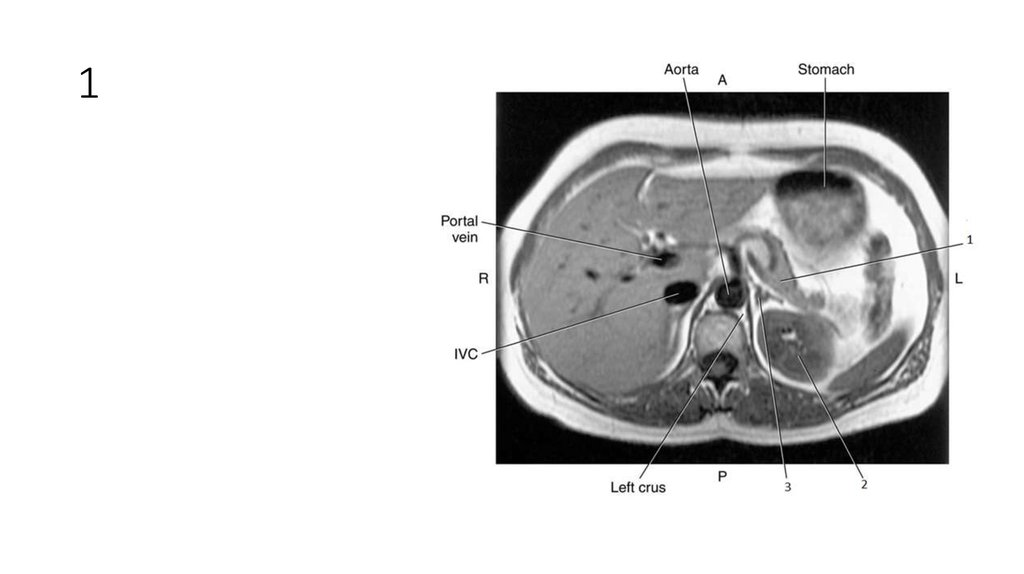

2. 1

3. 1

• Liver

4. 2

5. 2

• Spleen

• Inferior Vena Cava (IVC)

10. 1

11. 1

• Right Adrenal Gland